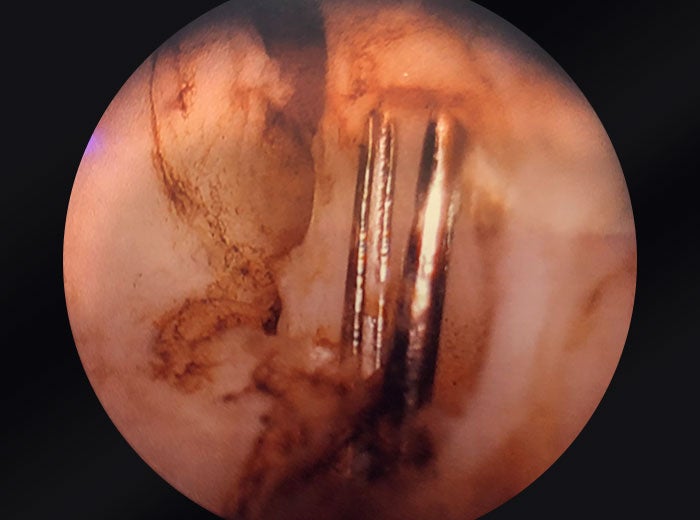

UroLift clips embedded in prostatic tissue

Images provided courtesy of Dr. Ricardo Gonzalez.

4 individual shots of an OR camera zoomed into prostate.

My step-by-step approach involves an enucleation versus vaporization incision technique to remove the clips. Traditionally, we begin with an incision at five and seven o’clock on the undersurface of the lateral lobe, that step is the same. And then the following step would be to make a counterincision on the anterior commissure of that same lobe. So if you do a five o’clock incision under the left lobe of the prostate, then you make a one o’clock laser incision down to capsule at the anterior commissure of that left lobe, you can identify the capsule and use the laser to peel the prostate lobe off of the capsule as you work from one incision towards the other. Working from the one o’clock incision down towards the five o’clock or from five o’clock to one o’clock behind the clip.

If you don’t have a morcellator, you would use the laser to divide that segment into smaller pieces that can be extracted with a grasper after the case, rather than using a morcellator. If you are going to use a morcellator, it’s important to try to remove the metallic parts like the stainless steel luminal side of the clip before morcellating the tissue that you have pushed into the bladder.

The steps to doing a trilobar enucleation for doing a PVP VIT procedure remain the same, but the purpose is to work around the clips to be able to excise them in the tissue, whether it’s en bloc, or in fragments that contain that tissue. In my practice, the most reasonable is to do the PVP VIT technique. The GreenLight laser not only cuts through the prostate tissue efficiently, but can cut through the PET portion of the UroLift implant to allow separation of the luminal stainless steel clip, along with the tissue that’s causing obstruction.

And then that procedure’s repeated on the contralateral side. So when the right lobe is treated, you make the incision at the seven o’clock position and 11 o’clock position and remove the tissue in between those two incisions. So the steps are functionally the same. The goal would be to avoid direct laser contact with the metal of the clip, because that may potentially damage the fiber.